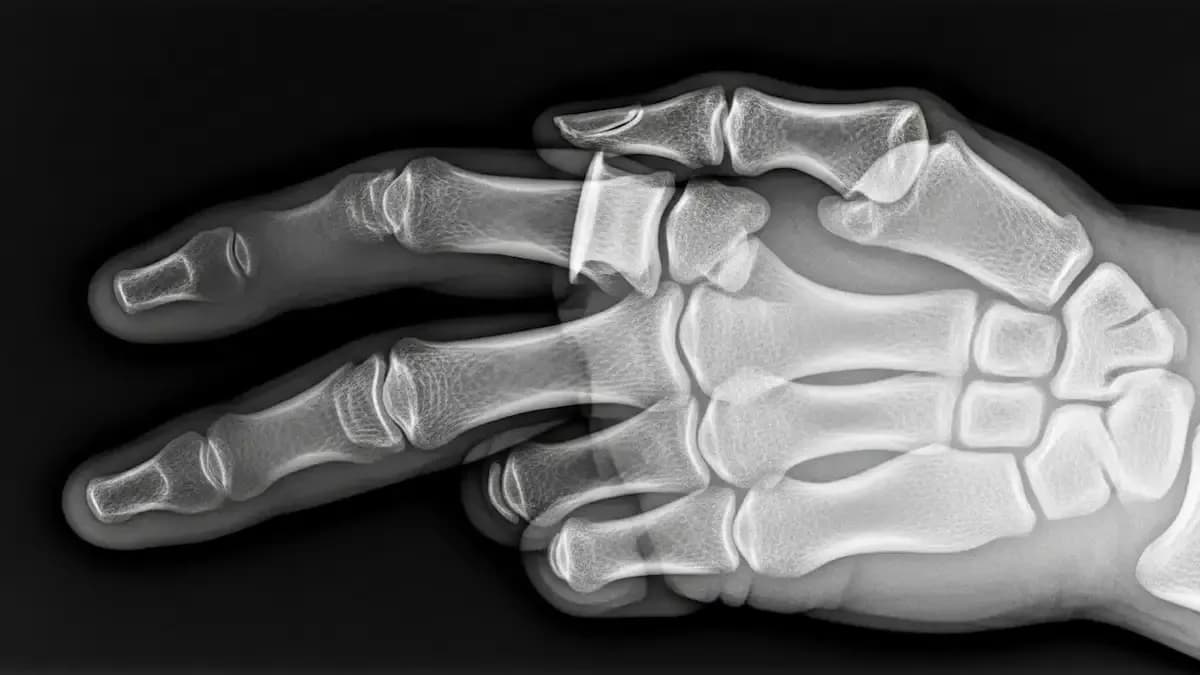

Fratura de boxer é o nome dado à quebra do colo do 5º metacarpo, o osso que liga o dedo mínimo ao punho. Ela costuma acontecer depois de um soco em superfície rígida, mas também pode surgir após quedas, pancadas…